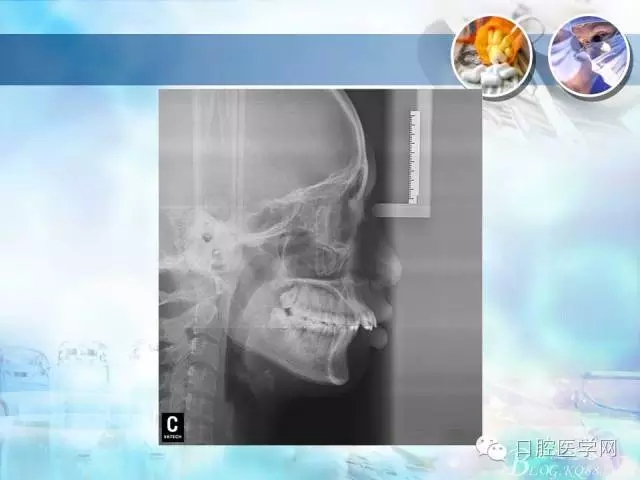

錯(cuò)合畸形中長(zhǎng)度不調(diào)的治療